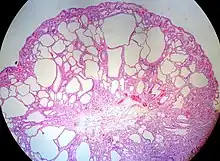

| Hyperplastic polyp of the stomach | Stomach | Elongated, tortuous, and cystic foveolae separated by edematous and inflamed stroma.[4] | ![]() |